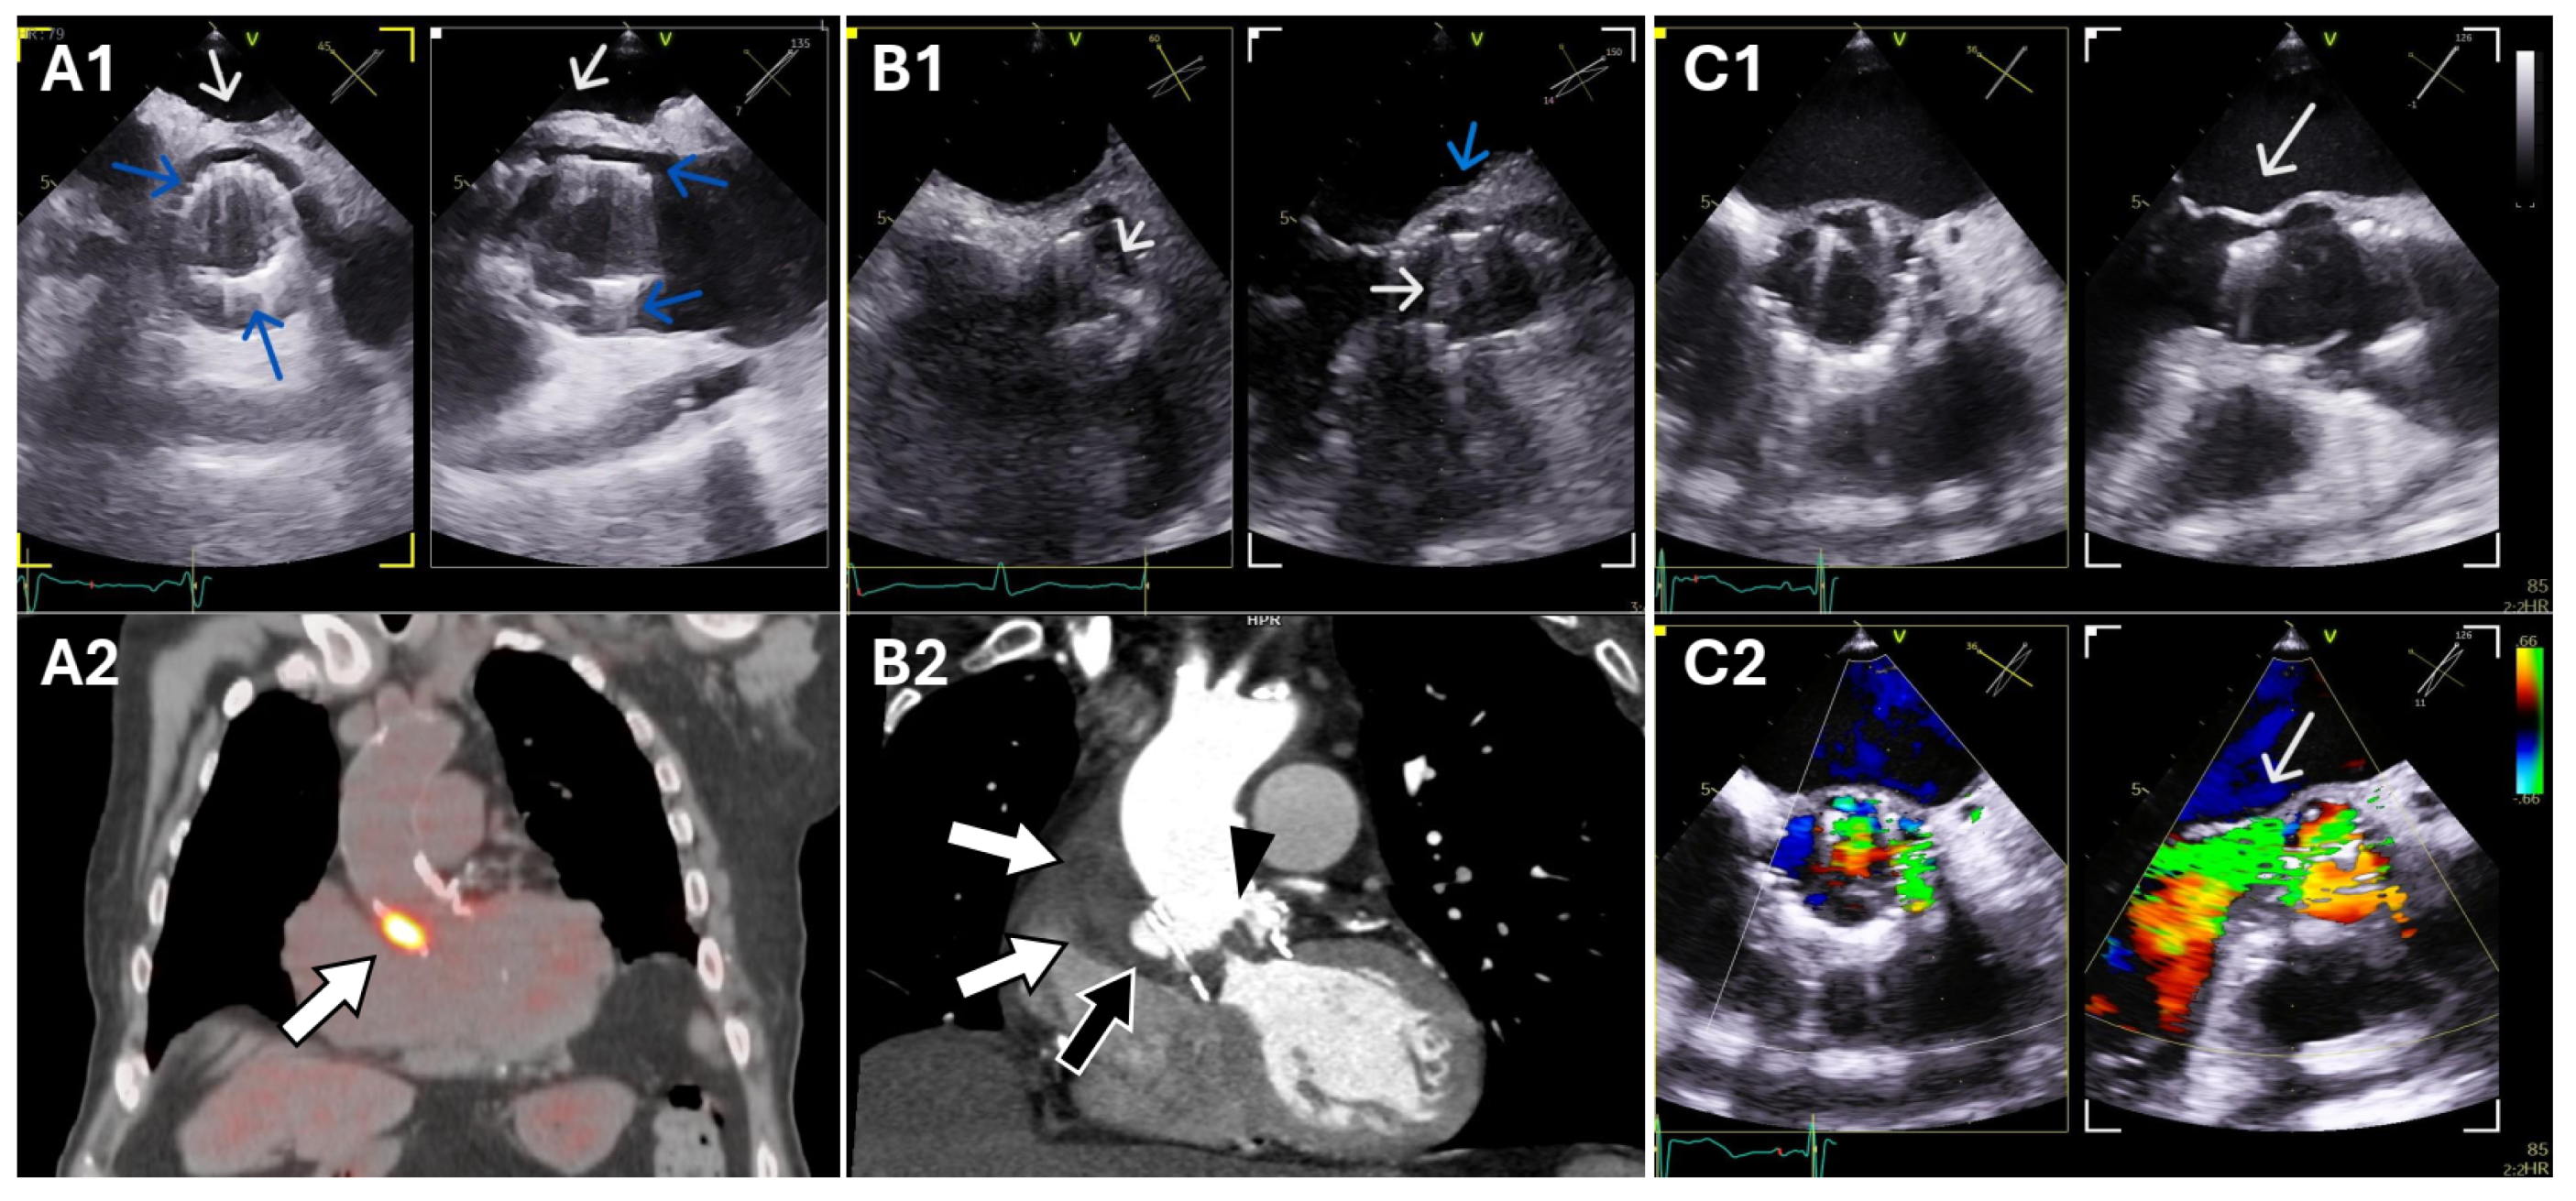

PET/CT can also identify the portal of entry of the infection of certain microorganisms, such as colonic lesions, which is particularly relevant in infective endocarditis, as eradication of the infectious source may prevent relapse and/or reinfections [47]. Furthermore, when endocarditis is ruled out, PET/CT can suggest an alternative infectious or noninfectious diagnosis. Another important advantage of PET/CT is that, when endocarditis is excluded, it can suggest alternative infectious or noninfectious diagnoses. Figure 1 presents three representative cases assessed by echocardiography and PET/CT.

Figure 1. Three cases of PVE in Perceval prosthetic valves. Panel (A1). Pseudo-sinus (blue arrows) and non-specific periprosthetic thickening (white arrow). Panel (A2). [18F]FDG-PET/CT fused image in the same patient showing intense FDG uptake on the prosthetic valve consistent with infection with periprosthetic involvement. Panel (B1). Leaflet thickening suggestive of vegetations (white arrows) and posterior periannular thickening (blue arrow); panel (B2). Corresponding cardiac CT confirmed vegetations (arrowhead) associated with periprosthetic and periaortic abscess (white arrows and black arrow). Panels (C1,C2). Perceval prosthesis dehiscence and severe paravalvular regurgitation (arrow). PVE, prosthetic valve endocarditis; [18F]FDG-PET/CT, 18F-Fluorodeoxyglucose Positron Emission Tomography/Computed Tomography; CT, Computed Tomography.